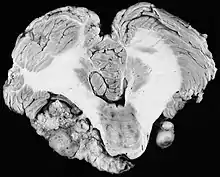

|  | |

| Bilateral schwannomas in a patient with neurofibromatosis 2 | |

For the most part, unilateral sporadic vestibular schwannomas are readily treated successfully by modern medical techniques. Having bilateral VSs is a more troublesome condition. Bilateralism is considered to be the hallmark and main diagnostic criterion of Neurofibromatosis Type II (NF2), a genetic disorder that is heritable, progressive, difficult to manage, and has a 1 in 2 chance of being passed on to each offspring. NF2 patients tend to have a more severe mutation, although there are mild mosaic cases in which only some cells carry the mutation. Genetic testing confirming mutation of the NF2 gene is recommended. About 50% of people with NF2 have a de novo mutation, and about 50% of these new mutations will be mild mosaic cases which are less likely to be passed on. NF2 patients may develop other cranial and spine tumors. NF2 develops during the teens or early adulthood, whereas sporadic VSs are diagnosed mostly in patients between the ages of 40–60 years. Both varieties of VS (sporadic and NF2) are very rare, accounting for only about 8% of all primary brain tumors. The incidence of NF2 is approximately 1 per 60,000 people.[6][7][8]